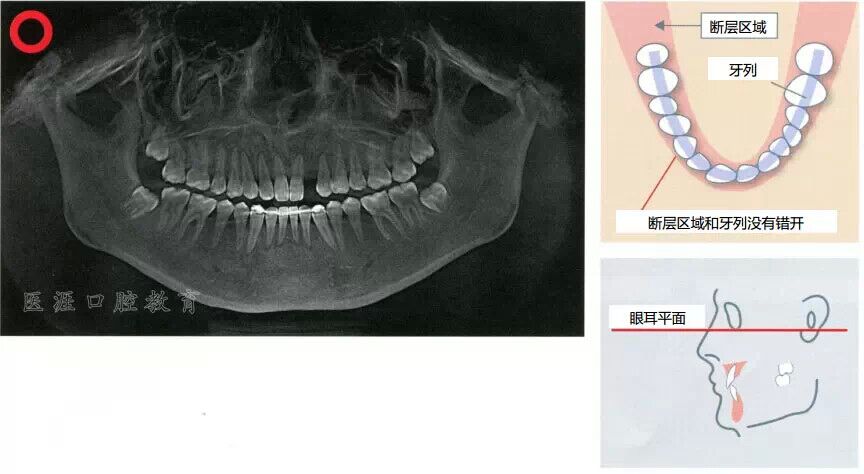

全景X光片

斷層區(qū)和牙列吻合的時候